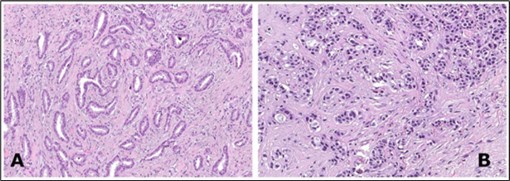

Staging of carcinoma breast as per American Joint Committee on Cancer (AJCC) 8th edition 3, 4. Figure 2

Figure 2.Tubular carcinoma delineating cords and cellular tubules lined by cuboidal to columnar epithelial cells imbued with miniature to intermediate nuclei, apical snouts and surrounding desmoplastic stroma 8.